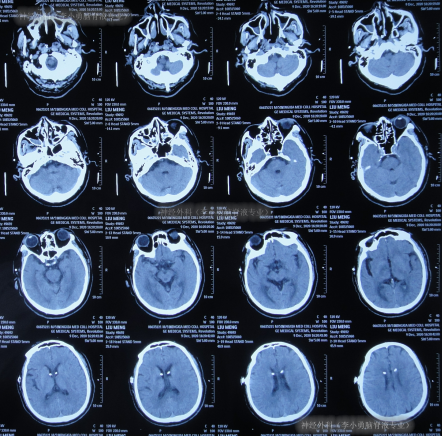

左侧脑室腹腔分流术后继续治疗10天,期间2次查头颅CT(图-9),虽意识基本正常,但记忆力差,吞咽动作慢,偶呛咳,小便失禁。

图-9:2次查头颅CT

左侧脑室腹腔分流术后即2020年12月28日出院,出院时仍记忆力差,吞咽动作慢,偶呛咳,例行检查头颅CT(图-10)后出院。

图-10:2020年12月28日头颅CT